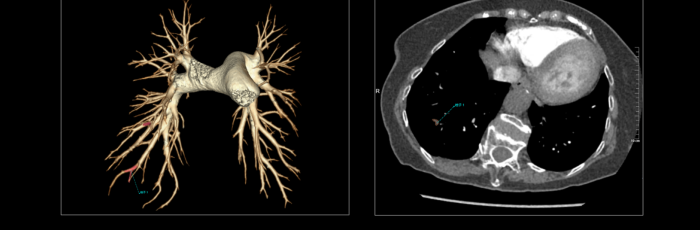

联影智能CT肺栓塞智能分析系统能够提供PE分诊预警、栓子检出和量化、肺血管智能分割和重建等功能,帮助医生及时诊断PE,鉴别诊断急性胸痛患者。同时,肺栓塞智能分析系统能够自动、准确地进行心室测量和肺动脉测量,提示右心室增宽和肺动脉增宽等PE相关风险征象,为早期PE检测和风险分层提供参考,辅助医生制定更优的诊疗方案,改善预后。

联影智能CT肺栓塞人工智能可一键智能分割、重建完整肺血管和栓子,360°展示肺动脉走行和栓子分布位置;高灵敏检出和定位栓子,提供量化分析,并自动计算RV/LV和PA/Ao,全面辅助诊疗,为PE的早期识别和临床风险分层提供强有力的智能工具;而快速分诊预警更是能够助力危急患者尽早进入诊疗环节。此外,AI可智能生成文本报告和归档图像,支持一键胶片打印。通过对救治全流程的加速优化,AI能够辅助医生快速识别隐匿肺栓塞,让胸痛患者跑赢生死竞速。